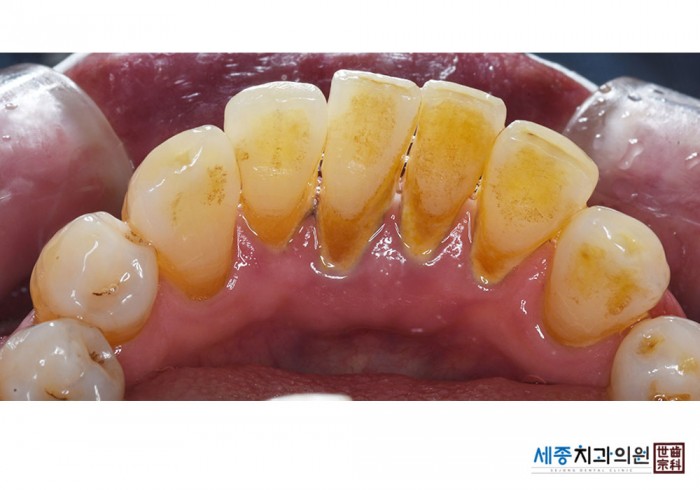

[스케일링] 치주질환 예방 스케일링

치료전 : 2023-01-04

가글마취&저주파 스켈러를 사용한 착색제거 스케일링